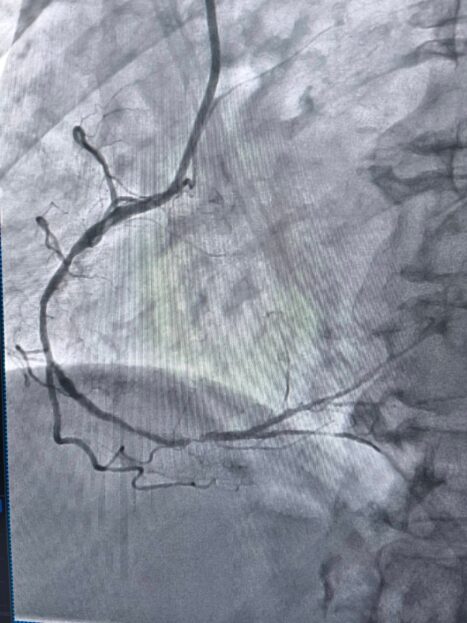

За словами завідувача відділенням інтервенційної радіології, кардіології та реперфузійної терапії Богдана Маслія, у пацієнтки діагностували значне звуження правої коронарної артерії. Розширити її традиційним способом – шляхом роздування балона, не вдалося, навіть із використанням балона високого тиску до 25 атмосфер (це приблизно у десять разів більше, ніж тиск в автомобільному колесі).

У таких ситуаціях на допомогу приходить ротаблятор – спеціальний пристрій із буром, покритим діамантовим напиленням. Він дозволяє «модифікувати» кальциновану атеросклеротичну бляшку, фактично шліфуючи її та відновлюючи можливість для подальшого стентування судини. Саме таким методом лікарям вдалося ліквідувати перешкоду в артерії та успішно імплантувати стенти.